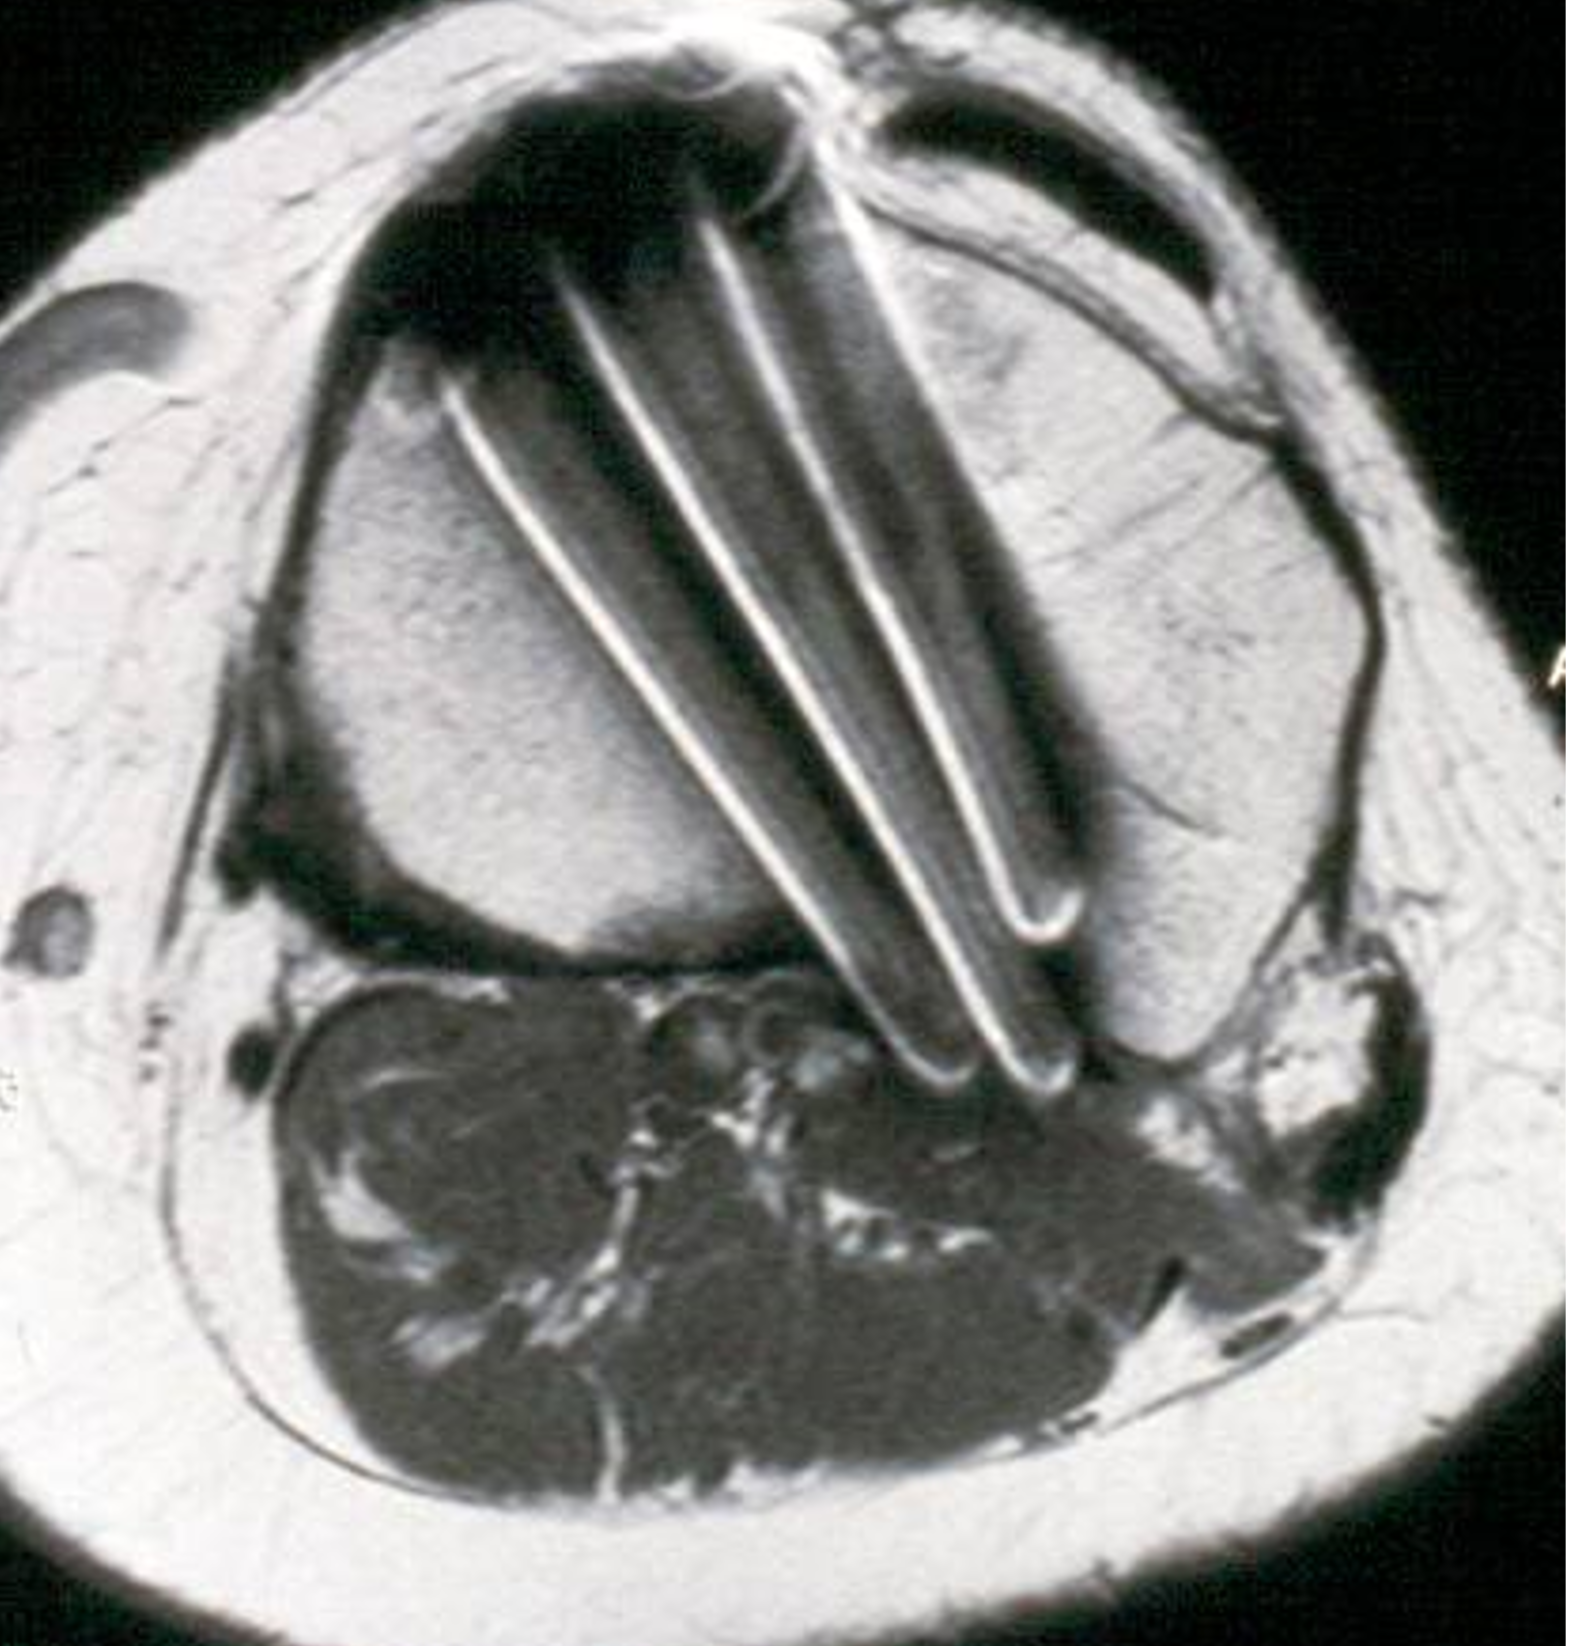

Arterial vascular complications: Klecker [33] reported in an MRI-based study of 1116 knee MRIs a 2.1% incidence of a high branching of the anterior tibial artery before the popliteal muscle with direct proximity to the posterior cortex of the lateral tibia (Fig. 10).

To prevent damage in these cases it is necessary to introduce a Hohman retractor or a special retractor under image intensifier control during the operation directly on the posterior bone along the osteotomy plane up to the lateral edge. Damage to the anterior tibial artery can cause a pseudoaneurysm and this might manifest as attenuation or absence of the dorsal pedal artery pulse. Therefore, preoperative and postoperative monitoring of the dorsal pedal artery pulse is very important.